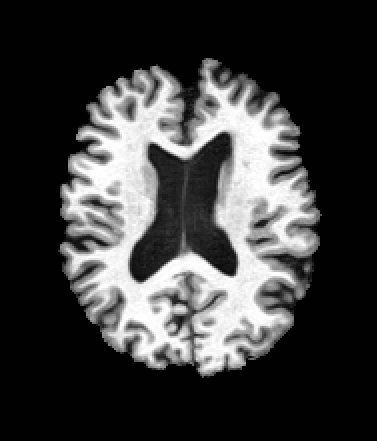

A trained MetaVoxel model can be unconditionally sampled by drawing Gaussian or categorical noise for each variable at timestep , and iteratively apply the denoising network until reaching . Unlike conventional diffusion models that focus solely on image generation, MetaVoxel can generate coherent synthetic patient profiles from the joint distribution , as shown in Figure 2.

| Age: 64.0 | Age: 53.8 | Age: 70.9 | Age: 76.9 |

| Sex: Male | Sex: Female | Sex: Female | Sex: Male |

![]() |

| Age: 80.9 | Age: 77.7 | Age: 73.2 | Age: 84.6 |

| Sex: Male | Sex: Female | Sex: Female | Sex: Female |